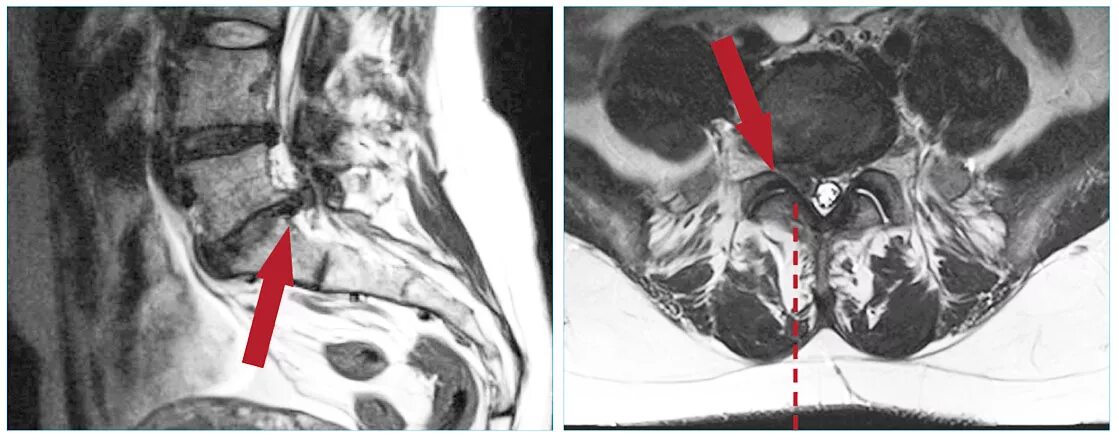

Грыжа экструзия диска l5 s1